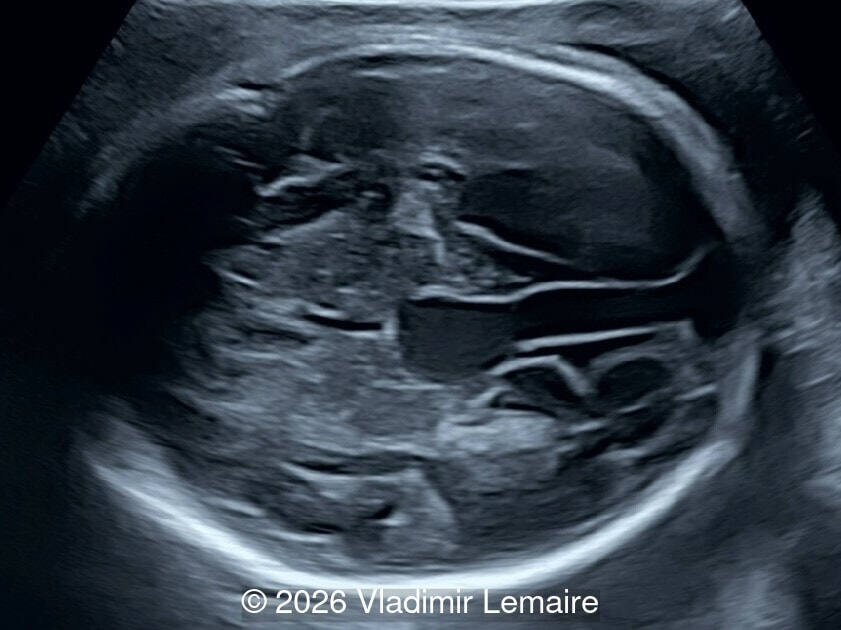

Axial plane of the fetal chest at the level of the four-chamber view.

Image 2 Axial plane of the fetal chest at the level of the four-chamber view.

Our imaging revealed enlargement of the fetal heart with dilation of the superior vena cava. On further evaluation, we identified an elongated anechoic cystic structure in the midline of the head, without mass effect on the surrounding structures. Color doppler demonstrated an arteriovenous fistula between the deep choroidal arteries and the embryonic median prosencephalic vein of Markowski. The vein of Galen aneurysmal malformation was likely the contributing factor to the cardiac enlargement. Cardiac function was, however, preserved and hydrops not present. Additional images are shown below.

On ultrasound, a VGAM appears as an elongated anechoic cystic structure in the middle of the head, often without mass effect on the surrounding structures. Color Doppler shows high-velocity flow in the lesion and can be used to identify the arteries feeding the vascular malformation. Pulsed-wave Doppler shows markedly turbulent flow. Additional key echocardiographic features include an enlarged heart with preserved systolic function, a dilated superior vena cava, and mild or moderate tricuspid regurgitation. Tricuspid regurgitation was not present in our case at the time of our evaluation.